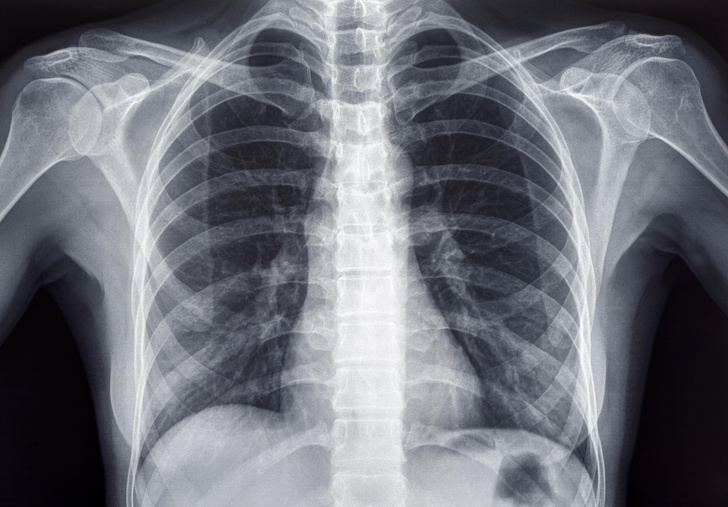

Иногда встречаются отклонения от нормы: примерно у одного из 200 человек появляется дополнительная костная дуга в области шеи. Такая особенность чаще всего не доставляет неудобств, но может вызывать давление на нервы или сосуды. Именно поэтому, когда кто-то спрашивает сколько ребер у человека, ответ может звучать как «24, но бывает и 25».

Ещё один частый вопрос — сколько ребер у человека при рождении, и меняется ли их количество со временем. Обычно с возрастом ничего не прибавляется и не исчезает, если не случилось травм или нет врождённых особенностей. Генетика иногда даёт сбои, и появляются лишние костные отростки — чаще всего у мужчин. Это опровергает распространённый миф, будто у женщин меньше элементов грудной клетки.

Чаще всего отличия от стандартного набора замечаются только при обследовании — например, на рентгене или КТ.